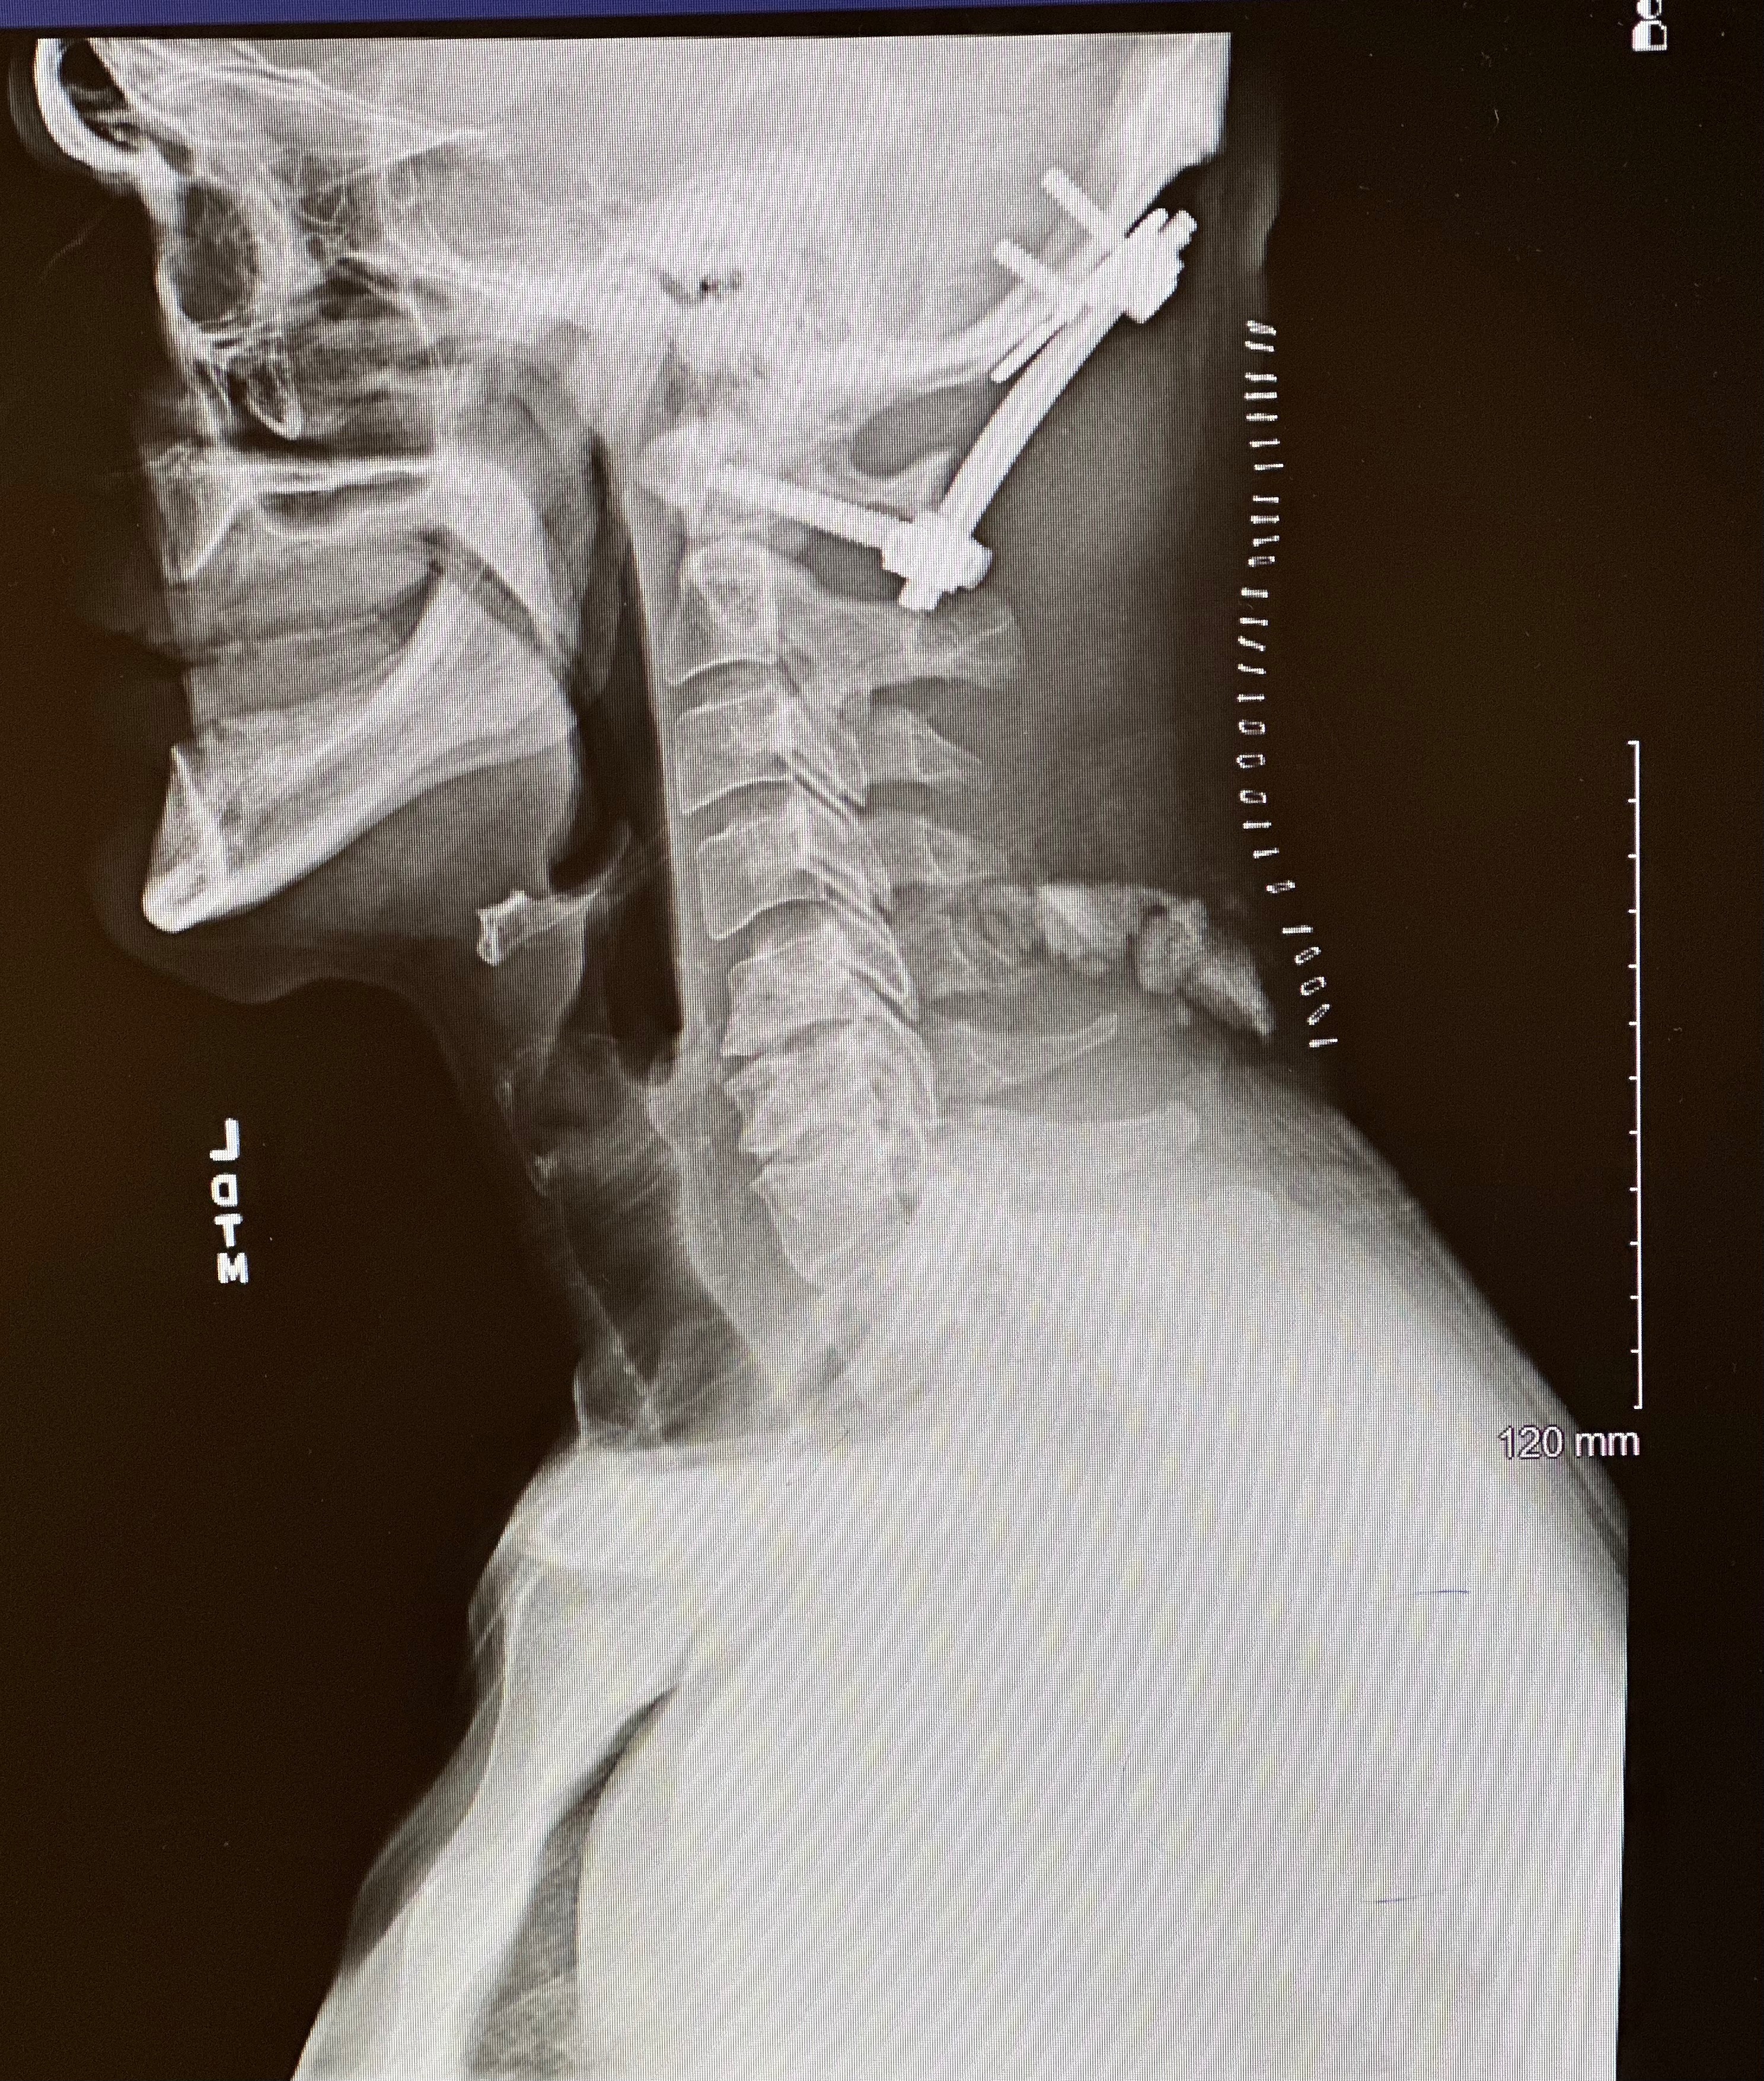

Prior to the brain surgery, in October 2024, Justin also had to undergo spinal fusion surgery due to the tumor’s involvement in his spinal column.

Near the end of 2024, their lives were turned upside down again when Justin was diagnosed with a massive meningioma brain tumor located in an extremely critical area of his brain and spinal column. In December, he underwent a 36-hour brain surgery, but surgeons were only able to remove about one-third of the tumor. Two-thirds of the tumor remains, as removing more would have caused catastrophic damage.